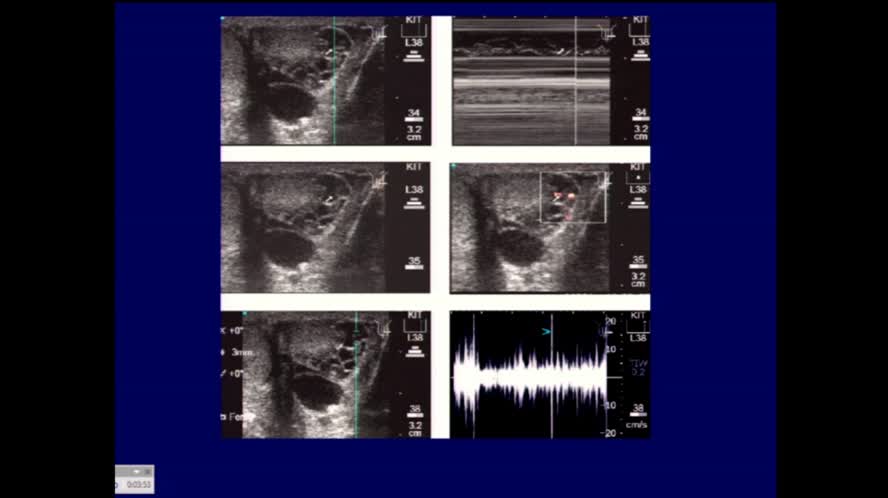

Ecografia nelle infezioni osteoarticolari

Congresso

: Ecografia Clinica nelle Malattie Infettive

Autori

: G. Serafini |

Data

: 21 marzo, 2016 |

Lingua

: ITA |